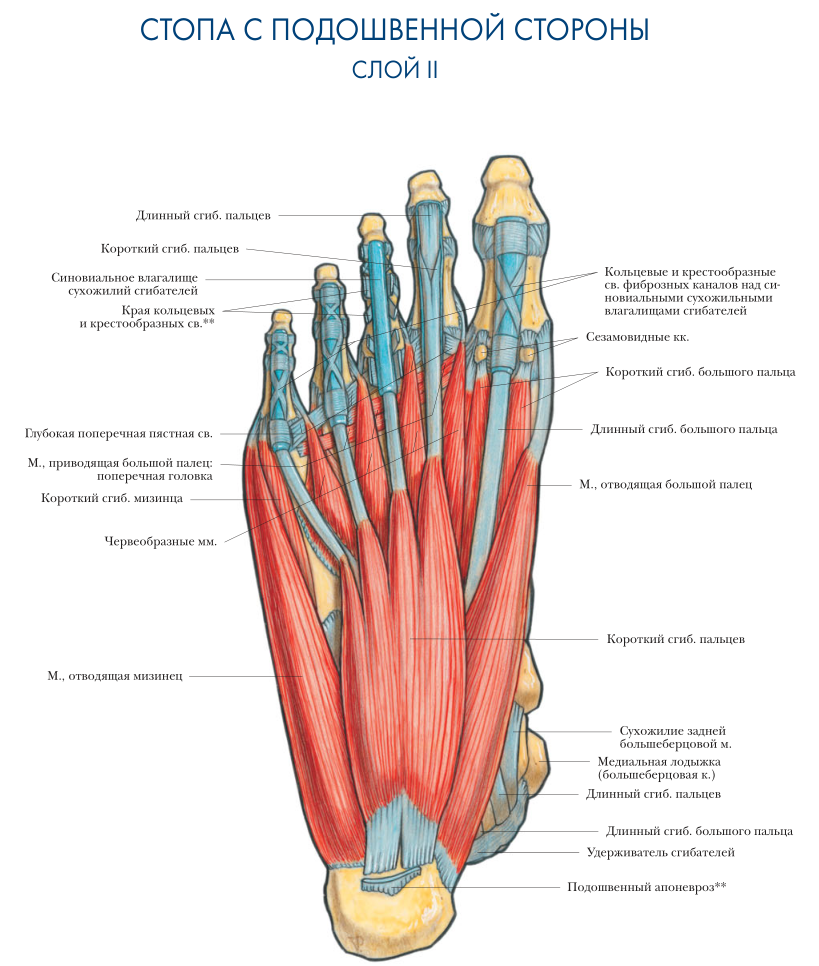

Анатомия подошвенной мышцы голени: подробное рассмотрение